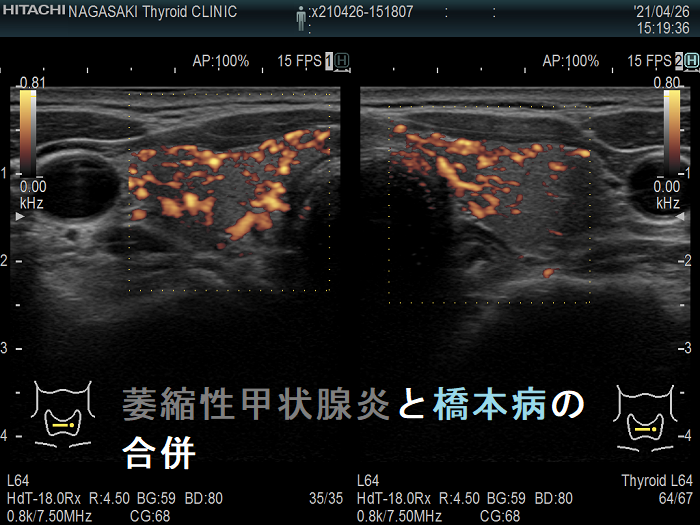

橋本病(慢性甲状腺炎)の自己免疫抗体である抗甲状腺ペルオキシダーゼ抗体(TPO抗体)・抗サイログロブリン抗体(Tg抗体)を同時に持っていると、橋本病(慢性甲状腺炎)の破壊で生じた甲状腺機能低下症なのか、萎縮性甲状腺炎による甲状腺機能低下症なのか判別が難しい。

橋本病(慢性甲状腺炎)を合併すると、甲状腺の萎縮が明らかでない場合がああります。

下記は、TSH 164 μIU/mL の重度甲状腺機能低下症女性。抗甲状腺ペルオキシダーゼ抗体(TPO抗体)・抗サイログロブリン抗体(Tg抗体)ともに陽性ですが、甲状腺超音波(エコー)検査で破壊の程度は軽く不自然です。橋本病(慢性甲状腺炎)の炎症があるため、甲状腺は委縮していませんが、TRAb 15.4 IU/Lの萎縮性甲状腺炎でした。